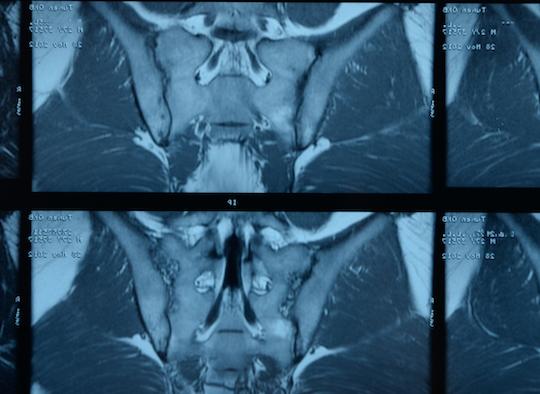

C’est la conclusion d’une étude de cohorte publiée dans Annals of the Rheumatic Diseases ayant suivi au moins 2 ans des lombalgies chroniques adressées à un rhumatologue. Le rendement des évaluations répétées est donc modeste globalement, par contre il peut être utile de répéter l'IRM chez les patients de sexe masculin qui sont HLA-B27+.

Chez les 552 patients souffrant de douleurs lombaires chronique, le diagnostic de spondylarthrite axiale a été posé d’emblée chez 175 (32%) et chez 165 (30%) à 2 ans, alors que le diagnostic de spondylarthrite a été exclu d’emblée chez 40% d’entre eux. Un HLA-B27+ et une imagerie de sacroiliite d’emblée ont permis de mieux prédire quels sont les patients qui seront atteints de spondylarthrite axiale avérée à 2 ans.

Le diagnostic initial est resté relativement stable au cours de ce suivi de 2 ans : le diagnostic initial de spondylarthrite axiale n’a été révisé que chez 5% des patients chez qui on l’avait posé, tandis que 8% des diagnostics douteux ont « progressé » vers un diagnostic avéré de spondylarthrite axiale. Une « bonne réponse » aux anti-inflammatoires non stéroïdiens (réduction de 50% au moins de la douleur lombaire en moins de 48 heures) et une sacroiliite en IRM se sont le plus souvent développées au cours du suivi chez les patients avec un diagnostic incident de spondylarthrite axiale.

Malgré la répétition des examens, l'incertitude diagnostique persiste chez 30% des patients lors du suivi sur 2 ans. Parmi les patients qui ont développé une sacroiliite en IRM, 7/8 étaient HLA-B27+ et 5/8 étaient des hommes. Ainsi, bien que la répétition des examens n’ait apporté qu'une aide « modeste » pour le diagnostic final, il semble que la répétition d’une IRM au fil du temps ne soit contributive que chez les hommes qui sont HLA-B27 positif, bien que ce soit un biomarqueur imparfait de la spondylarthrite.

Le bilan diagnostique comprenait l'évaluation des caractéristiques cliniques de la spondylarthrite, des protéines de l’inflammation, du HLA-B27, des radiographies et de l'IRM (articulations sacro-iliaques et rachis dorso-lombaire), avec des évaluations répétées. À chaque visite (au départ, à 3 mois, à 1 an et à 2 ans), les rhumatologues ont posé un diagnostic de spondylarthrite axiale ou d’absence de spondylarthrite avec leur degré de confiance (LoC ; 0-pas du tout confiant à 10-très confiant). Le critère de jugement principal était le diagnostic de spondylarthrite axiale avec un degré de confiance (LoC≥7 (d-axSpA)) à 2 ans.